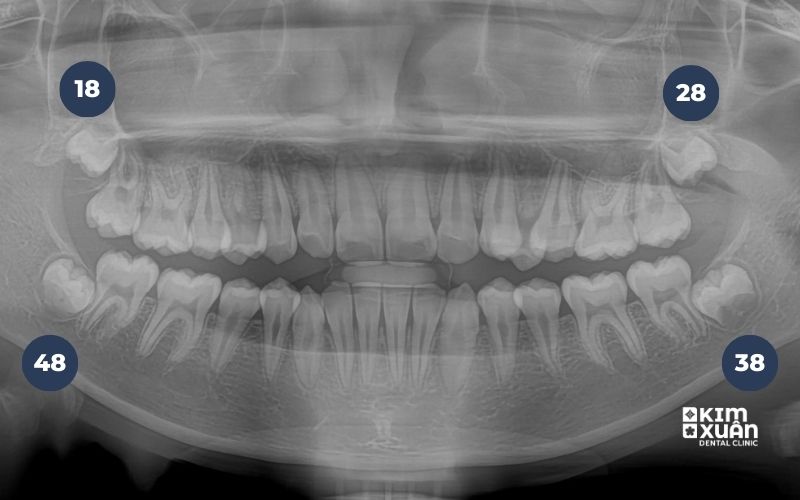

6. Cách Nhận Biết Răng Khôn Mọc Ngầm Chính Xác

Để xác định răng khôn mọc ngầm, cần thực hiện các bước sau:

Thăm khám nha khoa định kỳ nhằm kiểm tra tình trạng nướu, vị trí răng khôn và phát hiện sớm các dấu hiệu bất thường.

Chụp X-quang răng để xác định chính xác vị trí răng khôn trong xương hàm, hướng mọc, mức độ mọc ngầm và mức độ ảnh hưởng đến răng kế cận.

Đánh giá tổng thể kết quả kiểm tra, từ đó bác sĩ sẽ tư vấn phương án theo dõi hoặc chỉ định điều trị phù hợp với từng trường hợp cụ thể.

Trong nhiều trường hợp, răng khôn mọc ngầm không gây đau nhức rõ ràng nên rất khó nhận biết bằng mắt thường hoặc tự kiểm tra tại nhà. Vì vậy, thăm khám nha khoa kết hợp chụp X-quang vẫn là phương pháp chính xác và an toàn nhất để phát hiện sớm và phòng ngừa biến chứng.